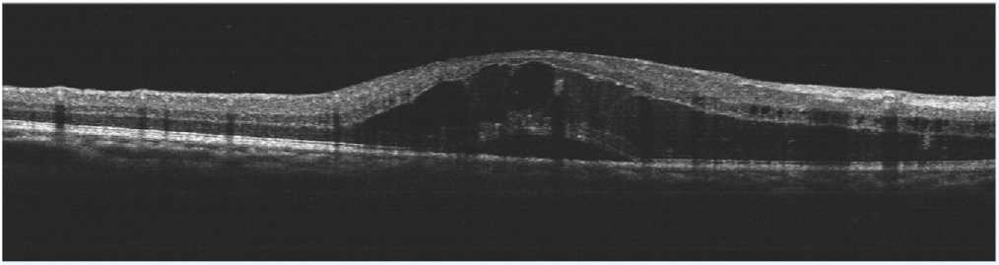

術前OCT檢查提示右(yòu)眼黃斑水腫(zhǒng)

術後OCT檢查(chá)提示(shì)右眼黃斑神經上(shàng)皮層厚度較前明顯變薄